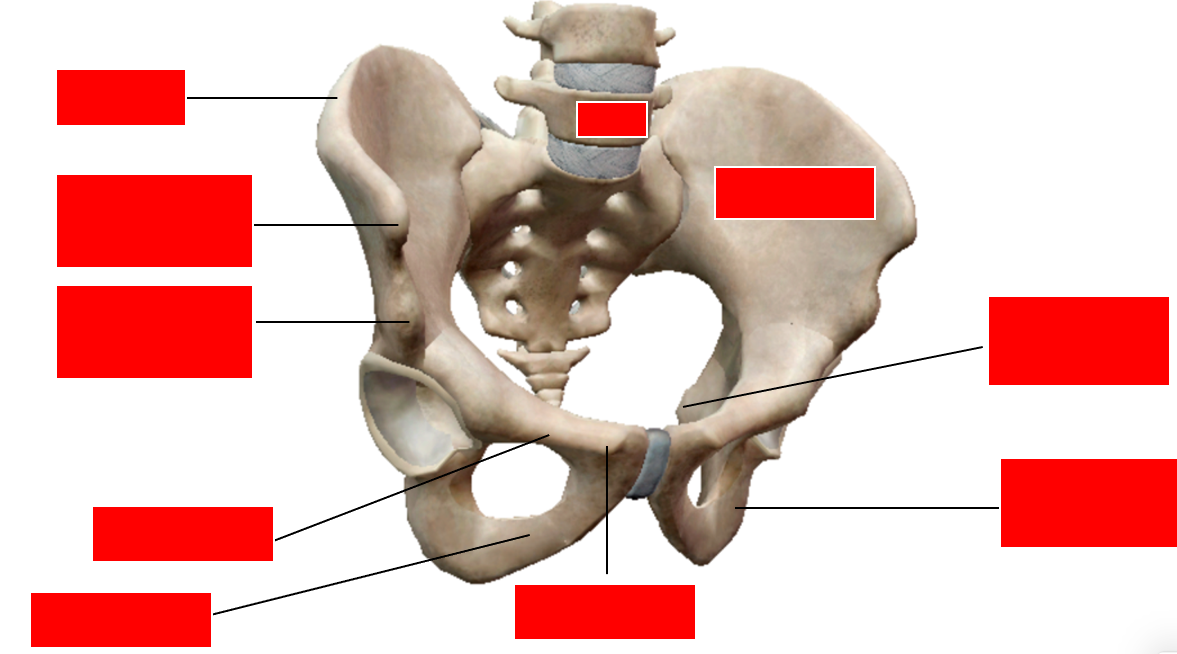

explain what is meant by the sacoiliac joint being a compound synovial joint [2]

explain what is meant by the sacoiliac joint being a compound synovial joint [2]

- *- anterior synovial plane joint**

- *- posteiror syndesmosis joint (**A syndesmosis is defined as a fibrous joint in which two adjacent bones are linked by a strong membrane or ligaments). stable joint !!

name for the ligament within the hip joint capsule? [1]

ligamentum teres [1]

Hip stability is due to: ? [7]

- Deep insertion of femoral head into acetabulum

- Strong tight articular capsule, this is loose in shoulder. Attaches to greater trochanter and neck of the femur, so is a very tight fit. Gives stability yet also restricts movement

- Ligaments around the joint capsule (especially anteriorly) which will help stabilise the hip joint in extension (the anterior ligaments).

- Large powerful muscles around joint: single, individual most powerful muscle in the body is the gluteus maximus, and the most powerful group of muscles (quadriceps) all work to stabilise the hip joint

- Ligament within articular capsule, ligamentum teres. This attaches the head of the femur to the acetabulum and acts as like a tether. Can also be called ‘ligament of the head of the femur’.

- Fat pad fills central region and adds cushioning for thinnest part of acetabulum. Also helps to keep these two bones together

- Acetabulur labrum is a fibrocartilaginous ring that helps with suction of the femur into the acetabulum. Doesn’t really add to the surface area, 10%, but acts with the synovial fluid to suction the head of the femur into the acetabulum

which is the strongest ligament around the hip joint articular capsule, which strengthens the joint? [1]

how does it achieve this stability? [1]

- anterior iliofemoral ligament - makes anterior side more stable than posterior

- relaxed in flexion but taught in extension

when the hip is extended, what happens to the ligament fibres? [1]

what does this do the the femur & acetabulum? [1]

when the hip is extended, what happens to the ligament fibres? [1]

- fibres become twisted and extended (& tighten)

what does this do the the femur & acetabulum? [1]

ligaments pull head of femur & acetabulum closer

what do we use to look at aligment of the hip?

shentons line: smooth arch from the superior pubic ramus to the inferomedial border of the neck of the femur